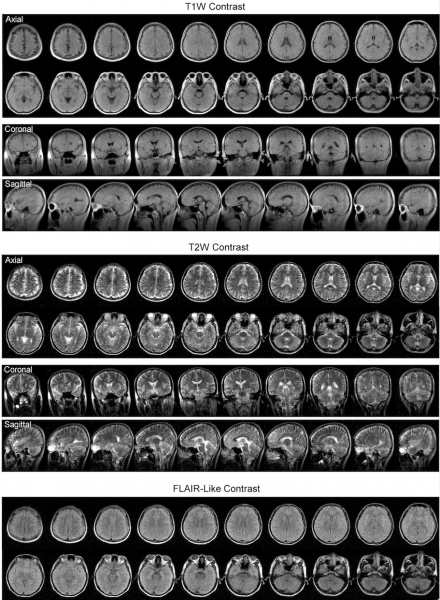

In collaboration with Professor Gilberto Leung of Neurosurgery and other clinicians at Queen Mary Hospital, his team had validated the results of using ULF-MRI by comparing them with images obtained from a standard 3 Tesla MRI machine. They could identify most of the same pathologies, including stroke and tumors results, despite the lack of clarity and resolution required for precision diagnostics.